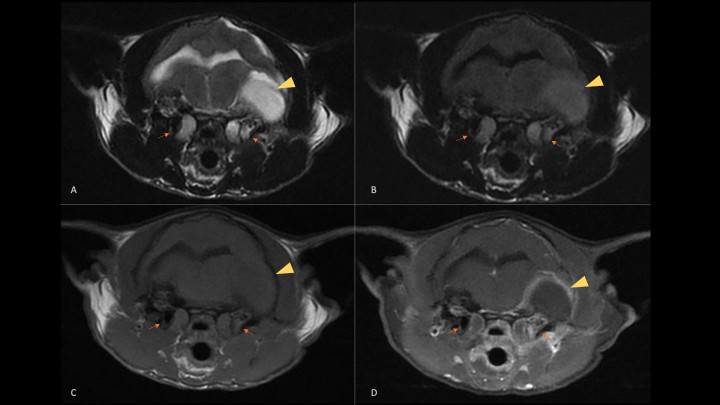

Estudio de resonancia magnética de una paciente felina con otitis media/interna y extensión intracraneal. Planos transversales de resonancia magnética en los que se observa contenido en ambas bullas timpánicas (flechas naranjas) y extensión intracraneal desde el lado izquierdo (cabeza de flecha amarilla). Dicha extensión da lugar a una lesión extraaxial con efecto masa, hiperintensa en T2W (A) y FLAIR (B), isointensa en T1W (C) con captación meníngea en la periferia tras la administración de contraste (T1W+C) (D) compatible con empiema. En este caso se trata de la paciente del vídeo 2C, que se presentó con un estado mental obnubilado, ataxia vestibular severa hacia el lado izquierdo, “head tilt” izquierdo, nistagmo vertical posicional y déficits propioceptivos en las extremidades del lado izquierdo, por lo que se sospechó de una lesión afectando al sistema vestibular central y lateralizada a la izquierda.